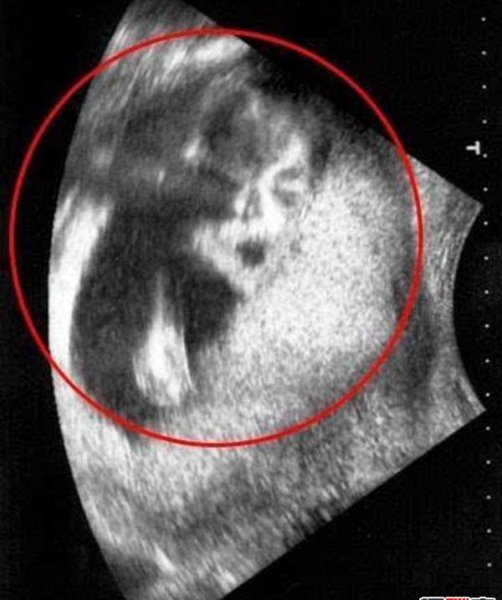

8、B超中发现迈克杰克逊的脸

2009年的11月,在英国有一对夫妇去医院为胎儿进行B超检查,竟然发现B超照片上有已经去世的歌王迈克杰克逊的脸,这让他们惊呆了。

他们立即去临近的格林顿·雷恩便利中心进行更仔细的检查。但是当扫描结果出来后夫妇两人被惊得目瞪口呆片子上已故歌王迈克尔·杰克逊正两眼直勾勾地“盯着”他们。

孕妇道恩·凯莉已经是6个孩子的母亲了,她说以前从来没发生过这种事情,感到的诡异。